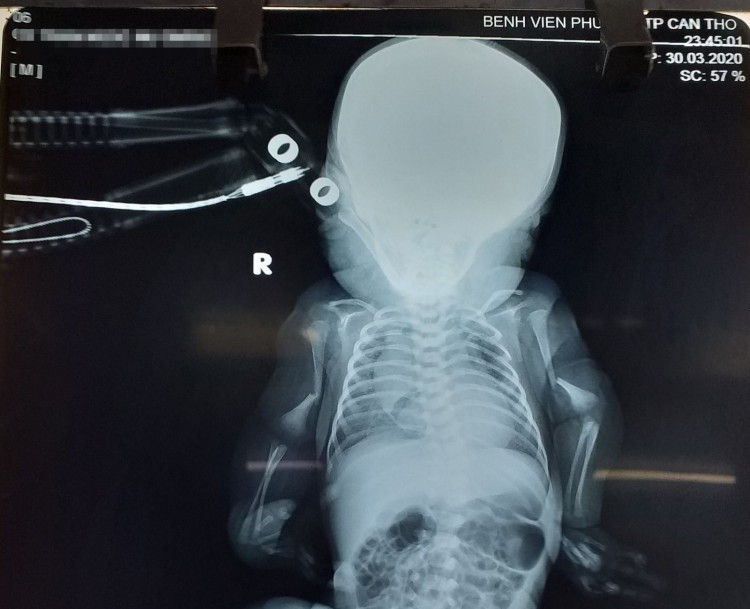

Ngay sau đó, bé được chuyển lên Khoa Nhi - Sơ sinh để tiếp tục theo dõi sức khỏe. Tại khoa, các bác sĩ thăm khám và làm các xét nghiệm, cùng với hình ảnh X-quang, ghi nhận bệnh nhi có hệ xương tứ chi biến dạng, vỏ xương mỏng, giảm độ đặc của xương, gãy xương tự nhiên (ảnh). Các bác sĩ chẩn đoán ban đầu bé mắc bệnh xương thủy tinh (Osteogenesis Imperfecta).

Theo bác sĩ CKII Nguyễn Thị Ngọc Hà, Trưởng khoa Nhi - Sơ sinh, bệnh xương thủy tinh do di truyền và đột biến gene tự thân ở trẻ. Nếu được phát hiện sớm, tư vấn tốt sẽ hạn chế tối đa các biến chứng và tránh được những bệnh lý bẩm sinh xảy ra ở những thế hệ tiếp theo. Vì thế, mọi người nên kiểm tra sức khỏe tiền hôn nhân và khi mang thai, chị em cần thăm khám thai định kỳ để phát hiện sớm những bất thường về di truyền cũng như dị tật bẩm sinh ở thai nhi.